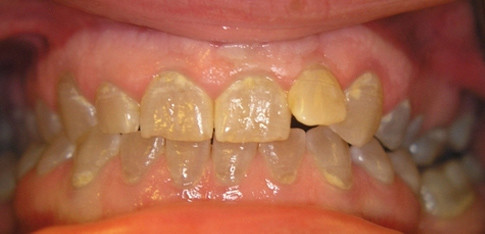

Im September 2008 kam die damals 19-jährige Patientin zur Erstkonsultation in unsere Praxis (Abb. 1). Grund ihres Besuches waren gelockerte Zähne der Oberkieferfront (11, 21, 22), wobei der Zahn 22 eine Wurzelfraktur aufwies, dies bei nur rudimentärer Ausbildung (Abb. 2). Klinisch und röntgenologisch zeigte sich das Bild einer Dentinogenesis imperfecta. Aus der Anamnese war zu entnehmen, dass auch der Vater (inzwischen zahnlos) und die jüngere Schwester Merkmalsträger sind. Auf Anraten des Vaters, der die ganze Palette einer konventionellen Prothetik schon hinter sich hat, erkundigte sich die Patientin gezielt nach einer implantologischen Lösung.